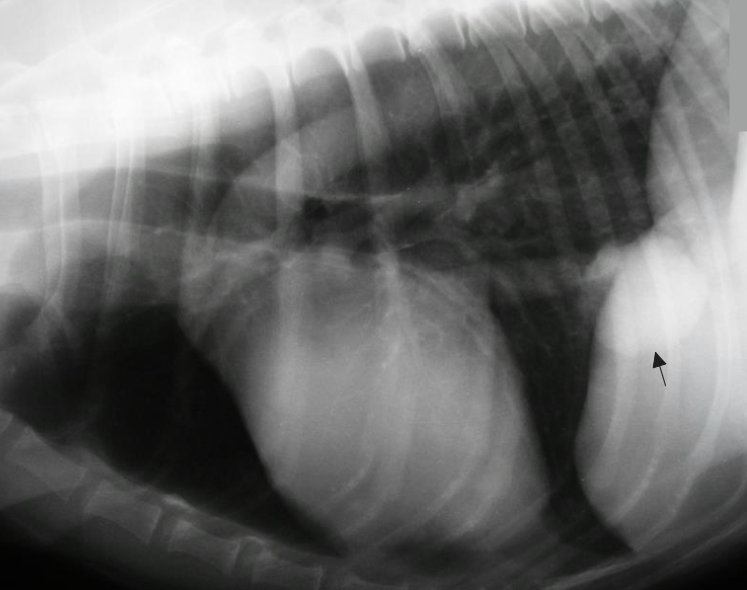

5. Lung lobe torsion

- Rt. middle lobe์์ ๊ฐ์ฅ common : Rt. cranial, Lt. cranial์ ๋ฐ๋ผ์ด

- Radiography : congested, consolidated lobe

- ์ ์ฒด๋๋ฉด์ ํ์ ๋ฐ์ ๊ฐ๋ฅ

- ์ ๋ฏธ(chylous)๊ฐ ํ๊ฐ์ ๋ชจ์

- Treatment : lobectomy - ํ์ด๋ฒ๋ฆฌ๋ฉด(untwist) ๊ณ ์ฌ ์๋ ๋ชจ๋ ๊ฒ๋ค์ด ์จ๋ชธ์ผ๋ก ํผ์ง๋ฉฐ ์ฌ๋ง ๊ฐ๋ฅ.